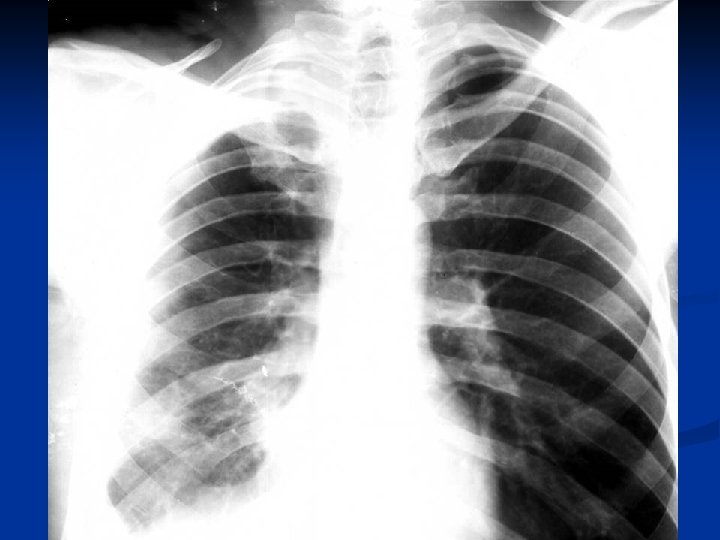

Distributie in functie de faza evolutiva

Complicatii Soc anafilactic intraoperator – 3 cazuri n Efractia chistului in cavitatea pleurala –

Complicatii Soc anafilactic intraoperator – 3 cazuri n Efractia chistului in cavitatea pleurala – 2 cazuri n Cheag postoperator – 1 caz n Pneumotorax – 4 cazuri n Decese – 1 caz n